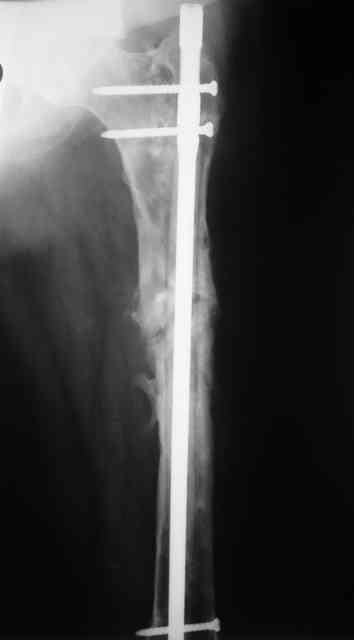

Для плечевой и большеберцовой кости - 10 мм, для бедренной - 12 мм.

Вчера наш пациент был на контрольном осмотре. Вроде все идет нормально. Рентгенограммы от 25 сентября 2007 г. (прошло 5 месяцев после операции) прилагаю.